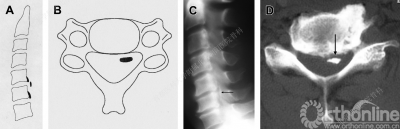

根据患者颈椎侧位片,可将OPLL分为以下四种类型:

A.连续型、B.混合型、C.节段型、D.局灶型

硬膜骨化(Dural ossification, DO)是后纵韧带骨化的一种特殊类型,它是由于骨化形成过程扩展到临近硬膜而导致临近硬膜骨化。DO的发生率约占OPLL的10%。根据DO的影像学形态特点,可以进一步将其分为以下三类:

孤立型:

双层型:

团块型:

术前了解DO的形态是很重要的,可以有效避免术中不必要的硬膜损伤。